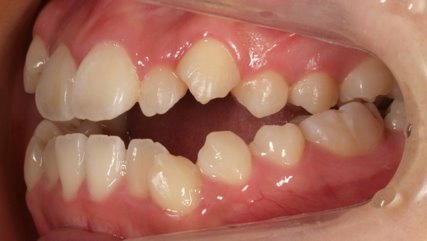

乱ぐい歯、でこぼこがとても酷い状態になります。歯が前後的に重なってしまっている、八重歯になっているなどがこのジャンルに入ります。

顎の大きさと歯の大きさのギャップが大きく、時には歯を抜かないと矯正治療ができない場合もあります。当院では治療期間が長くなるが抜かない治療方針など、一つの治療プランだけでなく、さまざまな可能性の治療方針を説明させて頂くよう心掛けております。こういった考え方はインフォームド・チョイスと言われ近年大切にされている考え方と言われております。

治療前

治療終了前